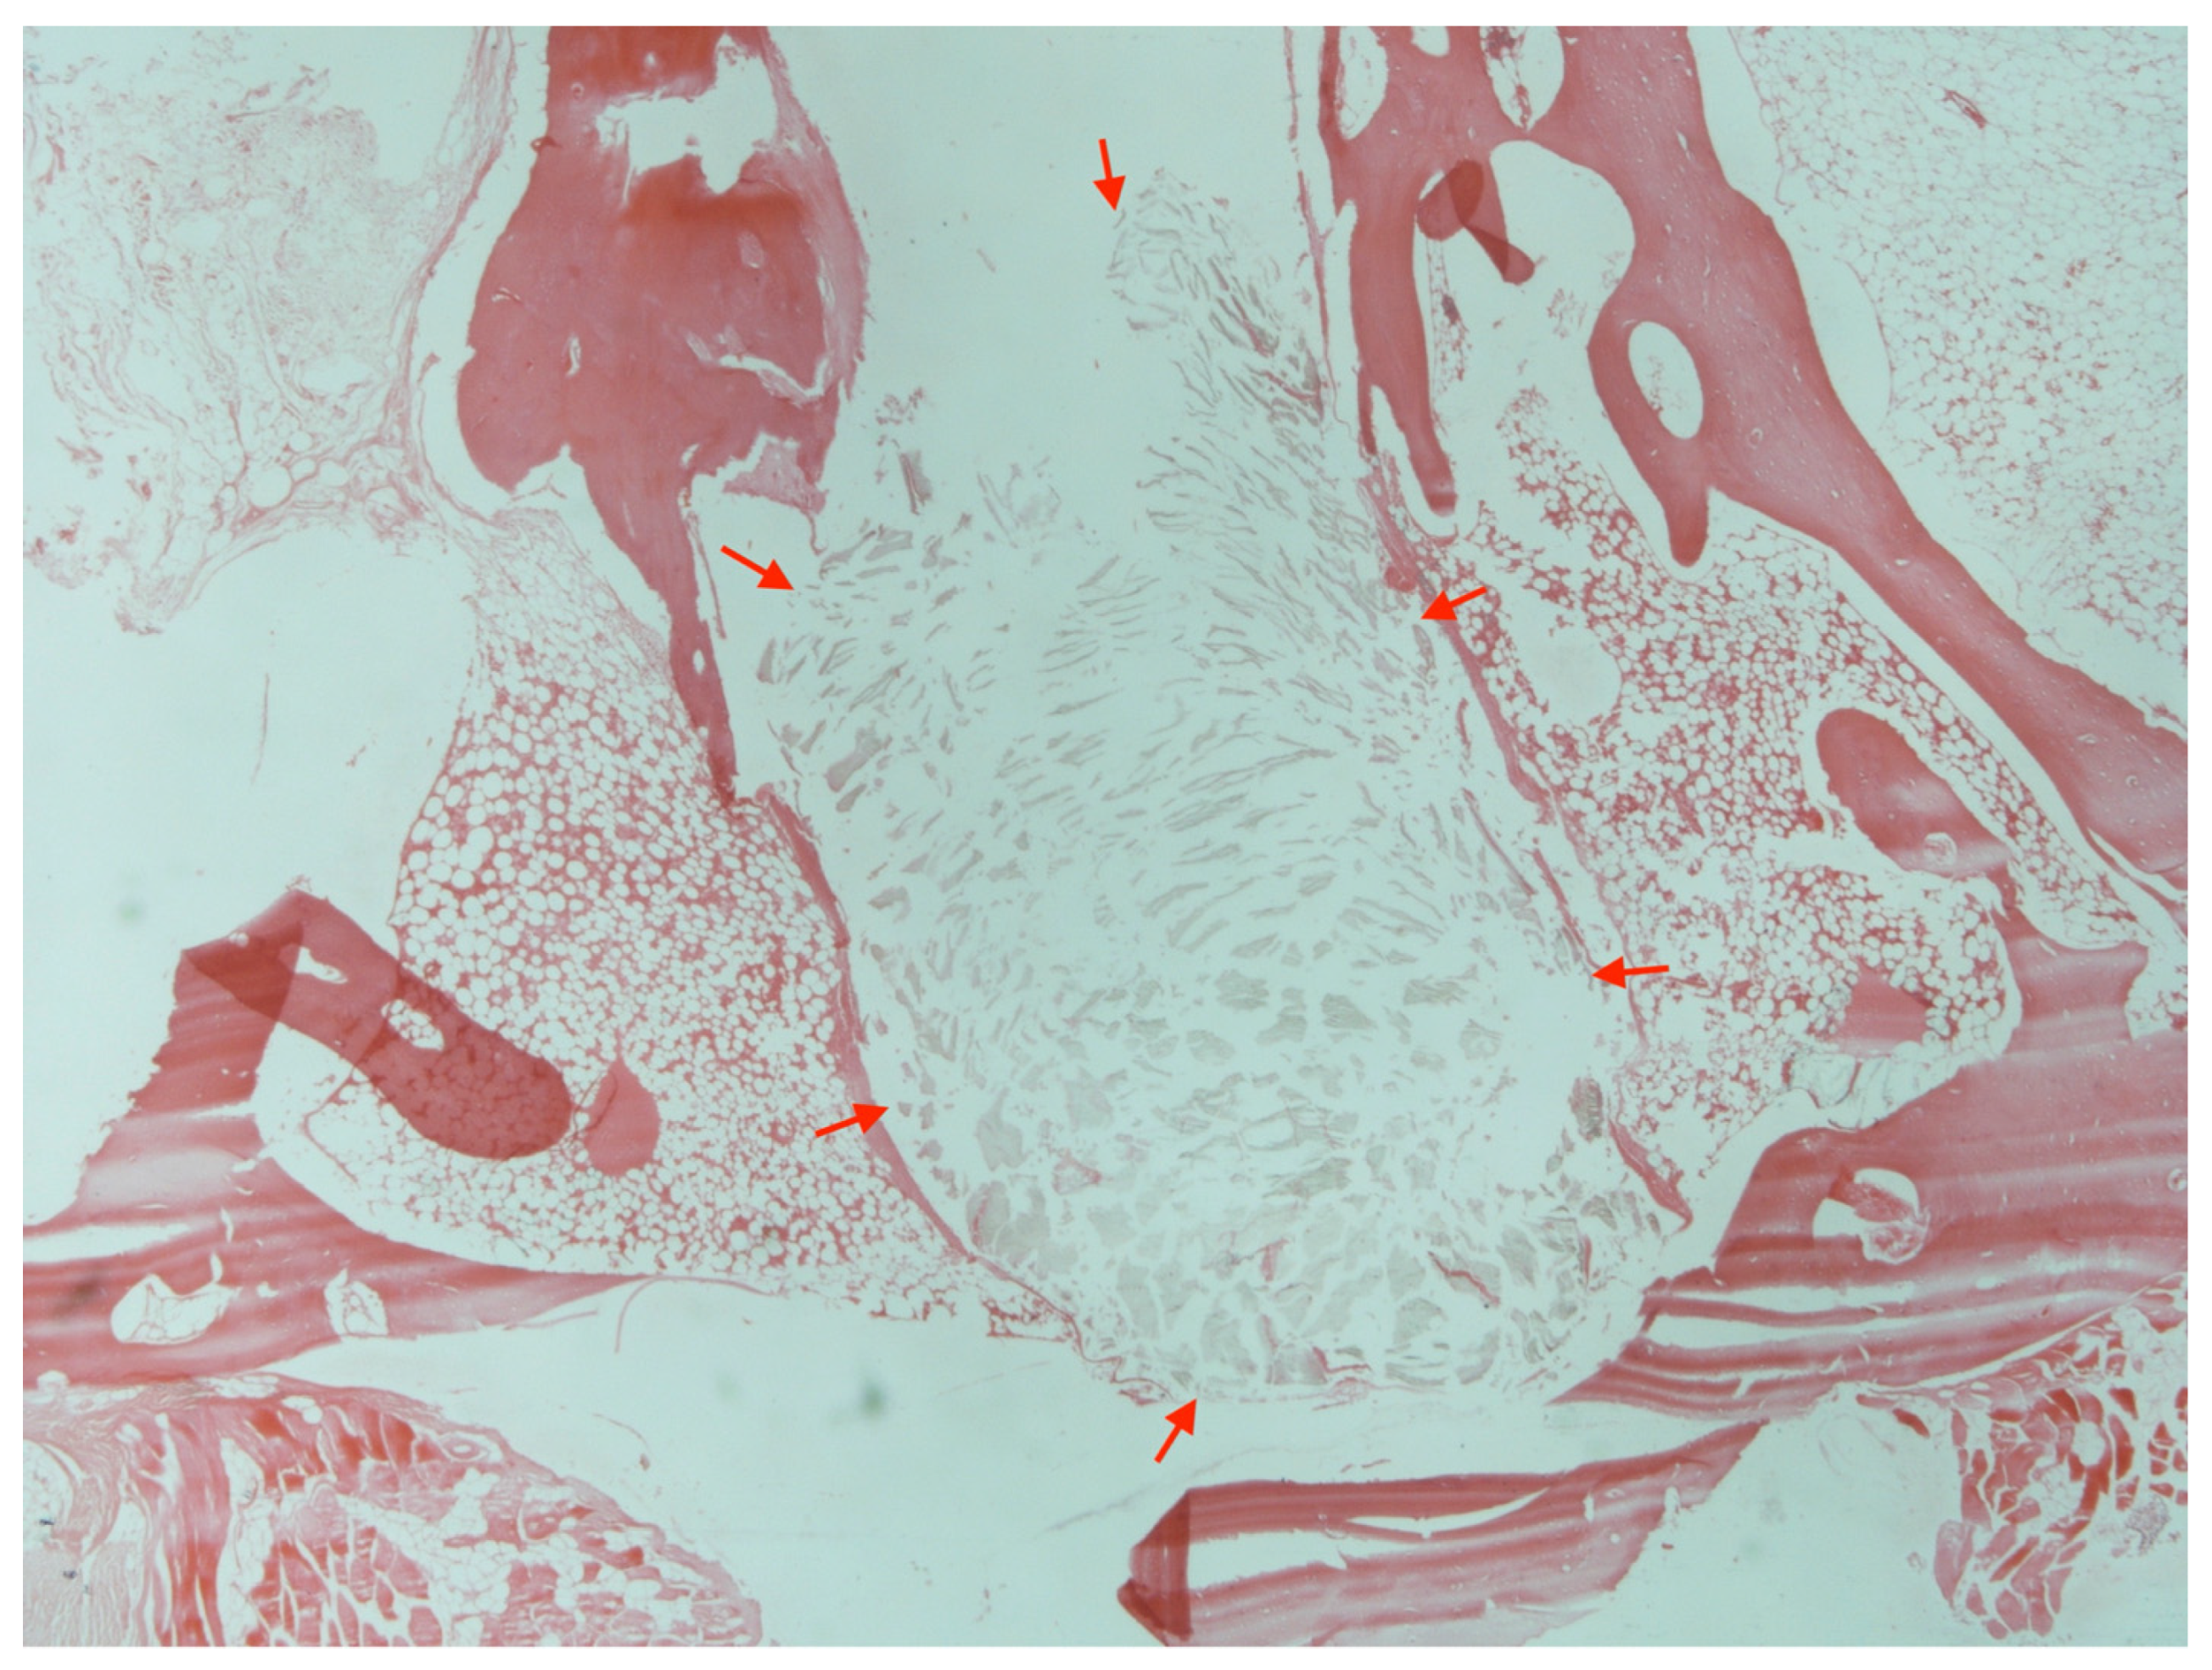

2.9. Histology

3.2. Foreign-Body Reactions

3.5. Histology